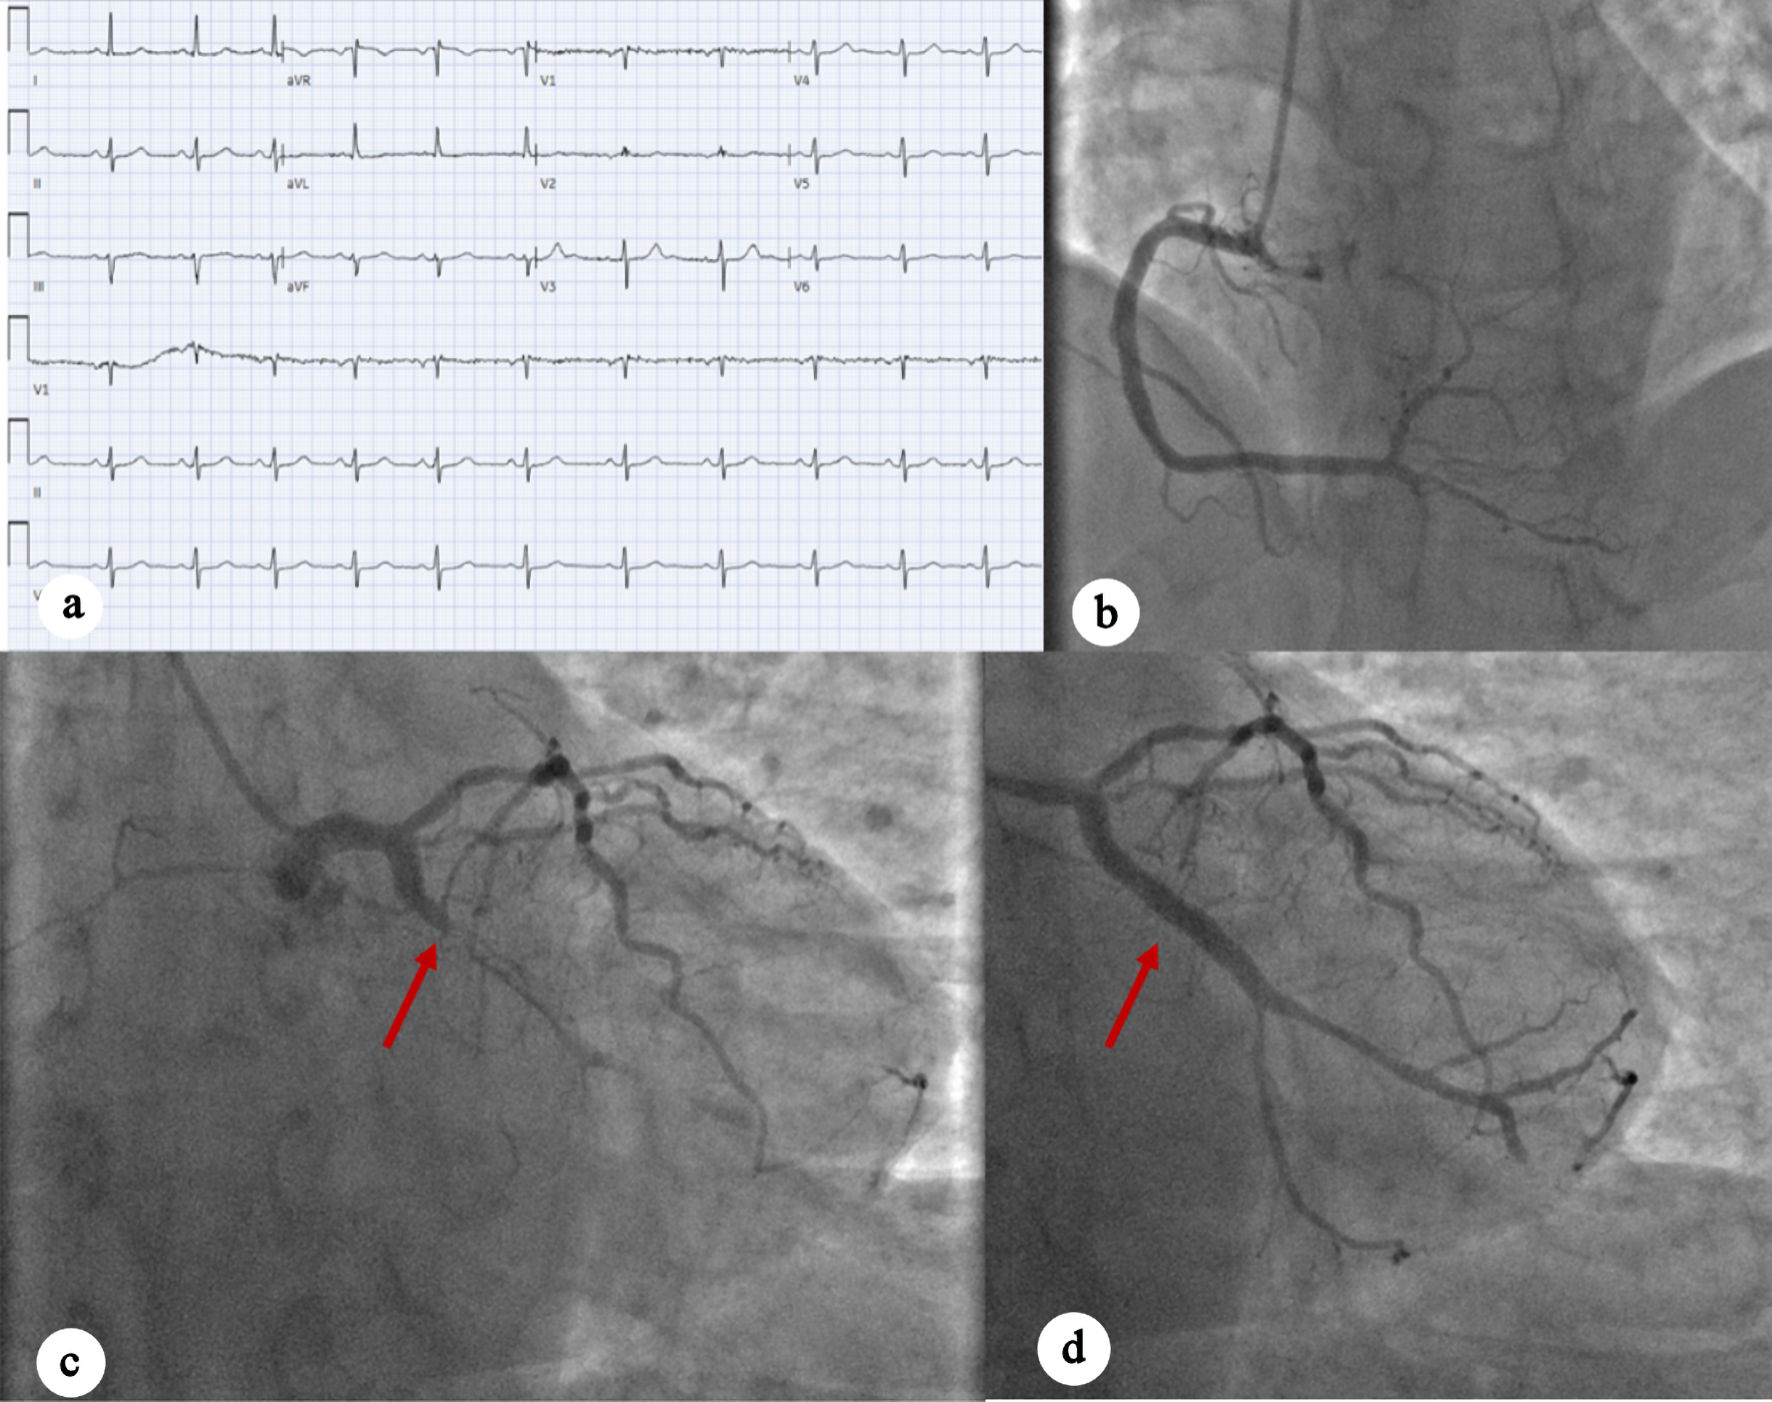

A 63-year-old male with a history of type 2 diabetes mellitus, hyperlipidemia, and insulinoma status post resection in 2000, presented to the ED with acute-onset abdominal pain that started the night before and persisted into the morning. In the ED, patient blood pressure was 150/94 mm Hg, computed tomography (CT) angiography of the chest and abdomen did not show any acute vascular or aortic pathologies. An EKG was done and initially interpreted as normal sinus rhythm with left anterior fascicular block (Fig. 2a). Cardiology was consulted for elevated troponin I to 13.72 ng/mL. On cardiology evaluation, POCUS showed a reduced EF and decreased wall motion of the inferior lateral wall on an apical view of the heart, which was confirmed on parasternal short-axis view. The IC team was promptly activated, and the patient underwent LHC, which showed a 100% proximal obtuse marginal artery occlusion with successful placement of a DES (Fig. 2b–d). The patient also had 60-70% moderate stenosis of the mid left anterior descending artery (LAD), with an instantaneous wave-free ratio suggesting the lesion was physiologically nonsignificant, and 50% moderate stenosis of the mid right coronary artery. Left ventriculography showed mildly reduced EF with anterior and lateral hypokinesis. The patient was transferred to CCU, where a formal TTE was done the next day, which showed normalized LV systolic function without regional wall motion abnormalities. The patient was discharged with follow-up.

Figure 2. (a) EKG showing normal sinus rhythm with no acute ischemic changes. (b) Left anterior oblique caudal view showing early-mid-RCA with moderate nonobstructive disease. (c) Left anterior oblique caudal view indicating complete occlusion of OM 100% occlusion, as well as mid-LAD moderate disease (red arrow). (d) Left anterior oblique caudal view showing post-PCI perfusion of OM1 (red arrow). EKG: electrocardiogram; RCA: right coronary artery; LAD: left anterior descending artery; OM: obtuse marginal artery; PCI: percutaneous coronary intervention.